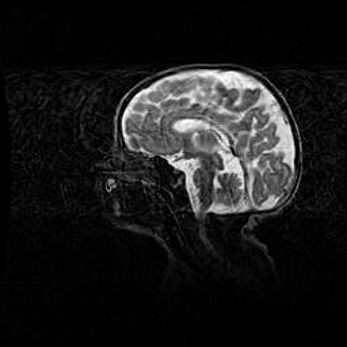

Аномалия Денди-Уокера. Признаки гипоплазии мозолистого тела.

Возраст: 5 месяцев 3 дня

Вес: 5550 г

Пол: мужской

Окружность головы: 39 см

Срок гестации: 40 недель

Аномалия Денди-Уокера – это порок развития головного мозга, для которого характерна триада симптомов: гипотрофия или аплазия червя мозжечка и/или полушарий мозжечка, расширение четвёртого желудочка с формированием ликворной кисты задней черепной ямки, гипертензионная гидроцефалия различной степени.

Гипоплазия мозолистого тела относится к дефектам внутриутробного этапа развития мозговой ткани, возникающим в процессе закладки структур головного мозга, что происходит на начальных этапах развития эмбриона.